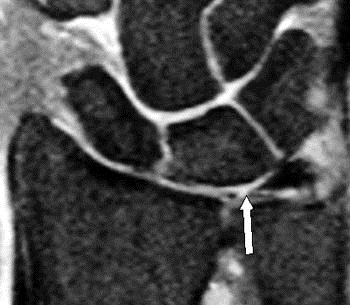

Cận lâm sàng

MRI là phương pháp chính xác, an toàn được sử dụng để xác định chẩn đoán. Trong khi đó, Xquang là phương tiện đánh giá ban đầu tốt để chẩn đoán gãy xương có liên quan.

Nội soi khớp cổ tay là tiêu chuẩn vàng để chẩn đoán, cho phép quan sát trực tiếp và điều trị ngay lập tức. [1]